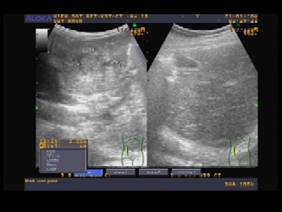

+ Siêu âm bụng: hạ phân thùy II, III có khối giảm âm không đồng nhất (d = 32x21mm), bên trong có trống âm (Hình 8a).

Hình 8a. Khối thương tổn giảm âm, bờ không rõ ở nhu mô gan

Hình 8b. Tổn thương nhu mô tiến triển với nhu mô gan đông nhất sau 1 tháng điều trị

+ Siêu âm bụng: hạ phân thùy III có khối giảm âm không đồng nhất d = 30x41 mm (Hình 8b).

+ Siêu âm bụng: hạ phân thùy III có khối tăng âm không đồng nhất d = 23 x 20 mm (Hình 8c).

Hình 8c. Tổn thương có hình ảnh tăng âm trên siêu âm đang dần hồi phục sau điều trị TCBZ

Bệnh nhân được chẩn đoán SLGL giai đoạn hồi phục và hẹn tái khám sau 3 tháng. Đồng thời, ca bệnh này đã được chẩn đoán xác định đủ tiêu chuẩn gồm các triệu chứng lâm sàng như đau bụng, buồn nôn, nôn, sốt cao từng đọt kéo dài một thời gian, chỉ số BCAT tăng trên 8%, xét nghiệm miễn dịch huyết thanh ELISA dương tính, dấu nhiễm trùng với sốt và bạch cầu chung rất cao, trên siêu âm có các hình ảnh thương tổn nhu mô gan ở hạ phân thùy 2-3 của gan (T) với đặc điểm giảm âm, kèm theo trống âm, không có bờ rõ ràng như trong áp xe gan amip.